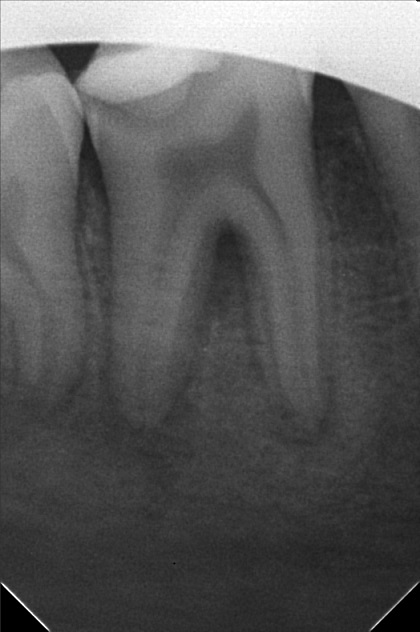

Edit Record Check our patient data records. Add patient information Patient Info Profile picture Last Name First Name Middle Name Birthdate Age Street Barangay City Country Zip Code Contact number Email Procedure 8/20/22- OP / RESTO #26 Oclusal & Disto lingual surface; #26 Occlusal & buccal pit/ EXO #65RF #46 10/19/22 - Ints of braces 50,000 less 3,999 (10,000) 11/19/22-ADJ 12/27/22-adj 01/22/23-ADJ 06/29/23-exo 14 *13 to extrude for laser/same wire 07/08/23- EXO #24 07/19/23- 14 NITI U/Lingual button #13/#13 extrude/16 Niti L 08/19/23- Extrude 13,same wire 09/16/23- same wire/ elastic Fox 13 to 43 to 44/18NiTi Lower 10/18/23- 14 NITI UPPER/ #13 BRACKET INSTALLED/ 18niti lower coil spring 44-45 ***request cbct 11/25/23- 16 NiTi U, 14 NiTi L #23 Observe all Lower towards right 12/22/23- 16 niti U/ 16 ss lower all lower move to right 01/27/24 ADJ reattachment 44 same wire adjustment all lower to the right 02/24/24 Adj-same wire chain lower reattachment #44 03/23/24 Adj reattachment #45 same wire class III elastic rabbit 04/20/24 Adj same wire chain lower 05/25/24 reattached #44 class III elastic penguin 18 SS lower w/ loop 06/20/24 #23 odontectomy near sinus 07/04/24 OP suture removal same wire class III elastic w/ loop rabbit .5 oz. 08/17/24 Reattached #44 #45 bite block 45/35 16 SS L class III elastic Q1/Q1v penguin 09/14/24 same wire 10/19/24 same wire reattached #15 11/16/24 same wire class III elastic rabbit 3oz 12/21/24 same wire chain L cross elastic Q IV to Q II 01/25/25 adj same wire reattached #35 slant elastic penguin 03/01/25 elastic slant penguin 18 SS L #35 reattached 04/09/25 elastic penguin 05/24/25 left class II rabbit right class II fox new bracket #35 reattached #11,#42 06/21/25 18 nITI U 16 SS L class III elastic chipmunk reattached #11,42 09/27/25 same wire reattached #32,15 11/15/25 Adjustment reattach #31, 32, 34 LC #34 - mesial #33 - mesial, distal #32 - mesial, distal #31 - mesial, distal #41 - mesial #42 - mesial #43 - cervical #44 - mesial 18 NITI lower Elastics- Rabbit 5oz QII-QIII class 3 12/27/25 Adjustment 02/07/26 18 SS lower Reattach #14 w/ class III Rabbit 5oz 04/15/26 Adjustment 16x16 Niti (U), chain (L) Rabbit 5oz, continue class III Replace new bracket #14, #32 05/15/26 Adjustment same wire P. chain (L) snip 34-35 rabbit 5oz for resto #44- B #41- M,D #42- D #25- O,M File abogado_kirsten.jpg File 2 abogado_kirsten_02.jpg File 3 audrey_kirsten_abogado.jpg File 4 kreistein_abogado.jpg File 5 File 6 File 7 File 8 File 9 File 10 File 11 File 12 File 13 File 14 File 15 File 16 File 17 File 18 File 19 File 20 Retain Record Retain Record Yes No Save Your Changes